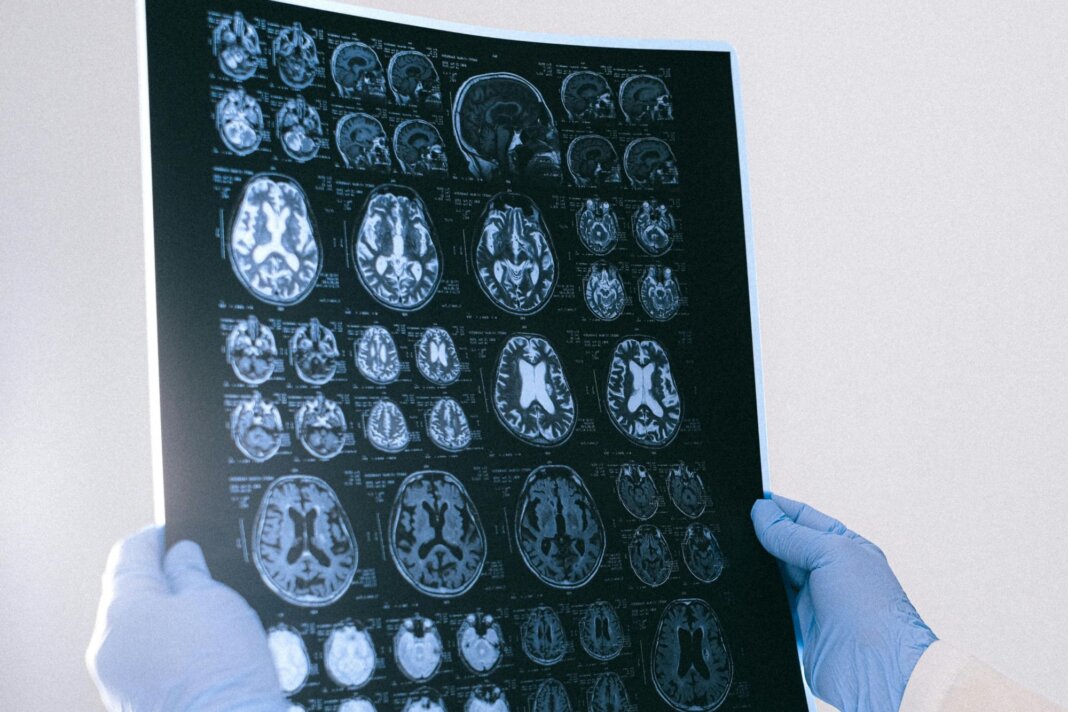

Qual è la scintilla iniziale che innesca il morbo dell’Alzheimer? A rispondere è un team di ricercatori della Harvard Medical School che potrebbe aver trovato nella carenza di litio nel cervello la causa scatenante della patologia. Lo studio, pubblicato su Nature, dimostra per la prima volta che il litio è presente naturalmente nel cervello, lo—Mondo

Alzheimer, un “metallo” aiuta a rallentare la patologia